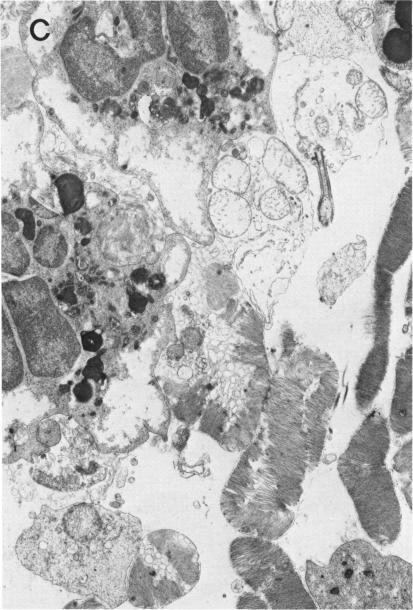

It is known that the visual loss in severe uveitis is due primarily to retinal tissue damage. In order to test the hypothesis that this damage may result from oxygen free radical-induced peroxidation of retinal membrane lipids, the generation of oxygen metabolites at the site of intraocular inflammation was investigated in an animal model of uveitis induced by retinal S-antigen. The effect of these metabolites on the initiation of retinal damage was characterized by histochemical, biochemical, morphologic, and morphometric methods. Light and electron microscopic studies at the early stage of the inflammation disclosed disorganization, degeneration, and necrosis of the photoreceptors and other retinal cells. Novel histochemical procedures demonstrated formation of superoxide and hydrogen peroxide at the site of uveoretinitis. Chemiluminescence measurements on uveoretinal tissue from these experimental animals revealed generation of superoxide anion and hydroxyl radicals. During the early phase of the uveoretinitis, concomitant with generation of the oxygen metabolites, there was peroxidation of retinal membrane lipids. The peroxidation products consisted of CD, MDA, hydroperoxides, and others. Associated with these changes was a selective depletion of the PUFA 22:6, decrease of which in the retinal composition has been shown to affect visual function. The morphologic and biochemical investigations clearly indicate that oxygen free radicals are generated at the site of uveoretinitis and that the retinal damage is mediated by peroxidation of lipids that are present in the retinal cell membranes. It would thus seem logical that such intraocular inflammation and the resultant retinal damage could be suppressed by antioxidant enzymes and oxygen free radical scavengers. These studies provide for the first time clear indication for developing new therapeutic agents that possess oxygen free radical scavenging properties, for treatment of human uveitis.

已知严重葡萄膜炎导致的视力丧失主要是由于视网膜组织损伤。为了验证这种损伤可能是由氧自由基诱导的视网膜膜脂质过氧化所致的假说,在视网膜S抗原诱导的葡萄膜炎动物模型中,研究了眼内炎症部位氧代谢产物的产生情况。通过组织化学、生物化学、形态学和形态计量学方法,对这些代谢产物对视网膜损伤起始的影响进行了表征。炎症早期的光镜和电镜研究显示,光感受器和其他视网膜细胞出现紊乱、变性和坏死。新的组织化学方法证明,葡萄膜视网膜炎部位形成了超氧化物和过氧化氢。对这些实验动物的葡萄膜视网膜组织进行化学发光测量,结果显示产生了超氧阴离子和羟基自由基。在葡萄膜视网膜炎的早期阶段,伴随着氧代谢产物的产生,视网膜膜脂质发生了过氧化。过氧化产物包括CD、丙二醛、氢过氧化物等。与这些变化相关的是多不饱和脂肪酸22:6的选择性消耗,视网膜成分中该脂肪酸的减少已被证明会影响视觉功能。形态学和生物化学研究清楚地表明,葡萄膜视网膜炎部位产生了氧自由基,视网膜损伤是由视网膜细胞膜中存在的脂质过氧化介导的。因此,通过抗氧化酶和氧自由基清除剂抑制这种眼内炎症及由此导致的视网膜损伤似乎是合乎逻辑的。这些研究首次为开发具有氧自由基清除特性的新型治疗药物以治疗人类葡萄膜炎提供了明确的依据。